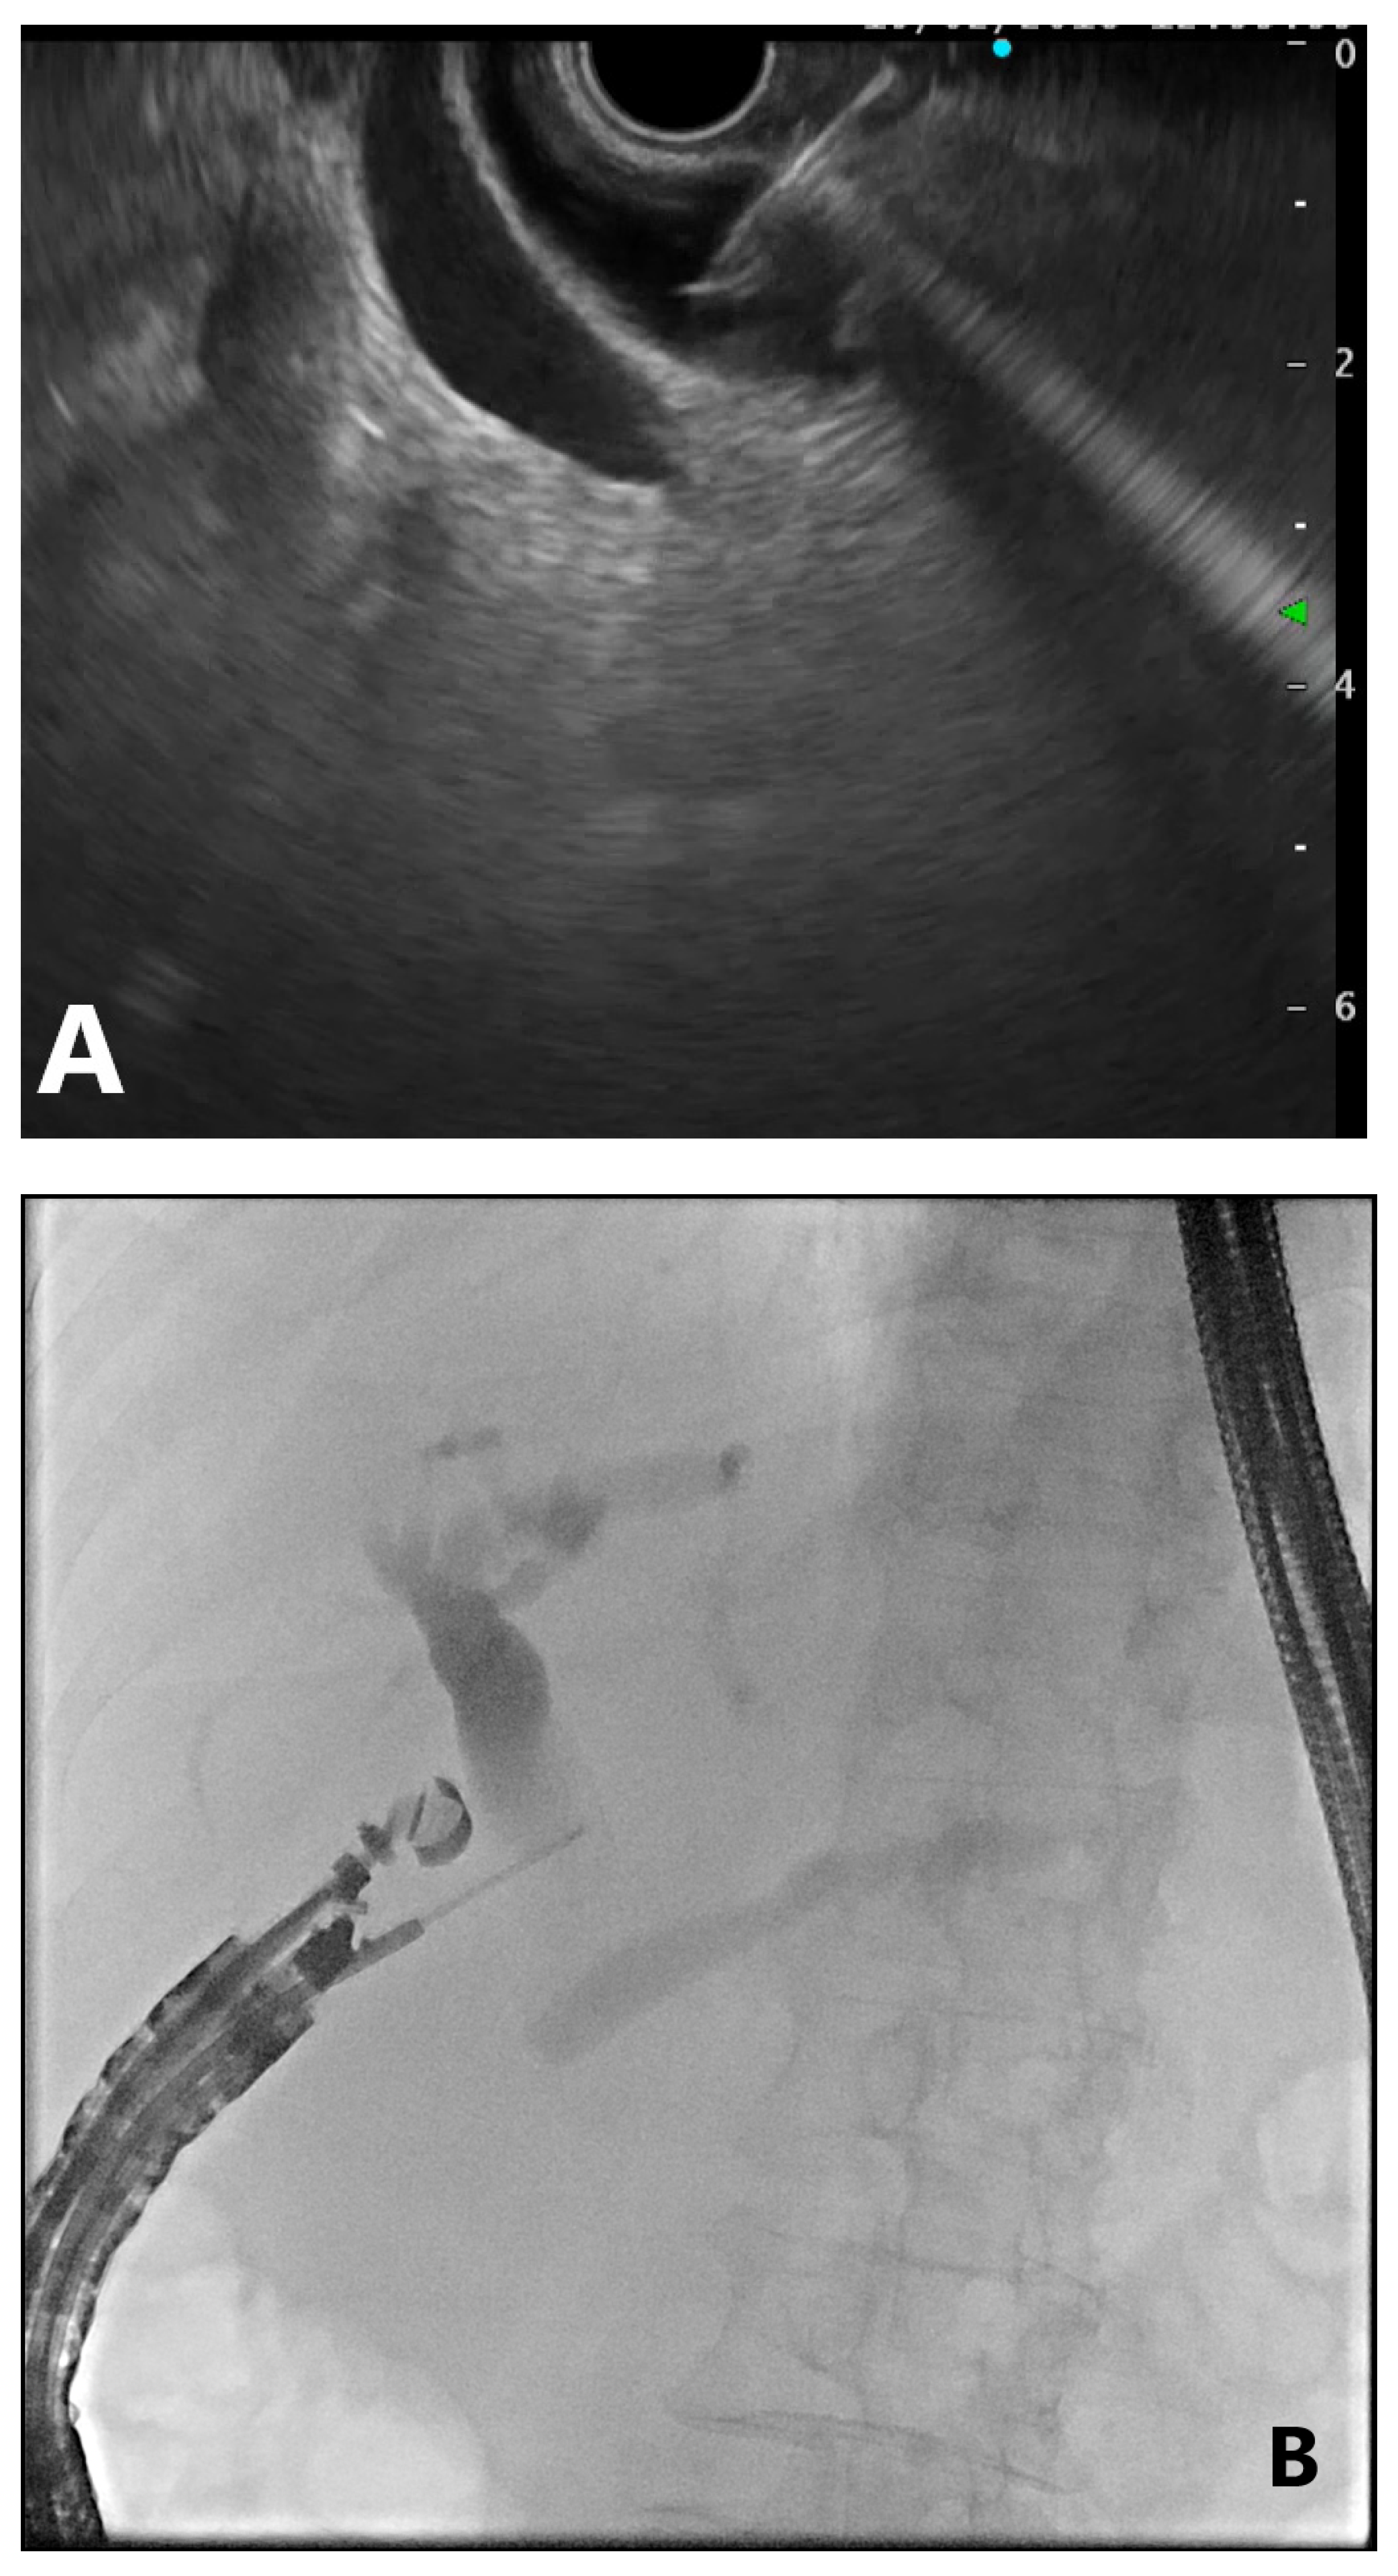

4. EUS-Guided Rendezvous (EUS-RV) Technique